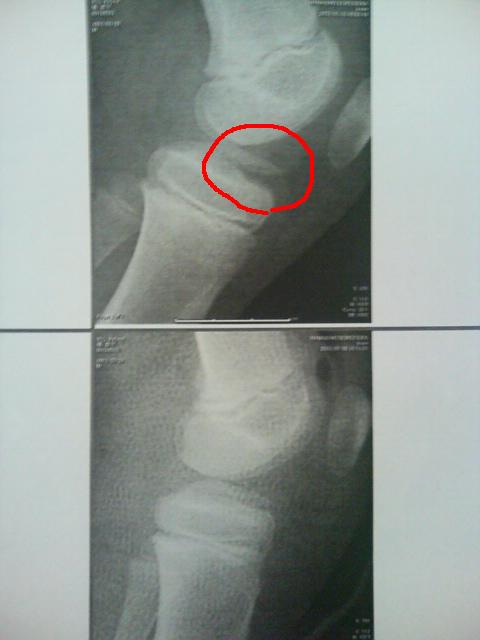

レントゲン 手術前後

上が手術前、下が手術後。赤○が 骨折したとこ